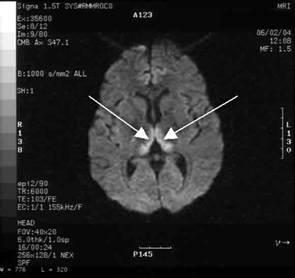

She made a rapid clinical recovery. Visual acuity returned to normal within 3 days and her ataxia, gaze limitation and neuropathy improved. Repeat MRI imaging 7 days later showed moderate resolution of the hyperintensities. Our patient went on to successfully deliver a healthy baby girl at 37 weeks’ gestation.

Our case is unusual in that visual deterioration was the first symptom of an evolving thiamine deficiency. There was a delayed presentation of the classical triad of Wernicke’s encephalopathy — ataxia, mental confusion and ocular gaze problems. Moreover, in our case, MRI scanning was able to detect sensitive neurological changes, raising the suspicion of thiamine deficiency. This information was important in prompt treatment of the condition when clinical signs began to emerge. Indeed there are reports of the usefulness of MRI imaging in diagnosing cases of Wernicke’s encephalopathy.7